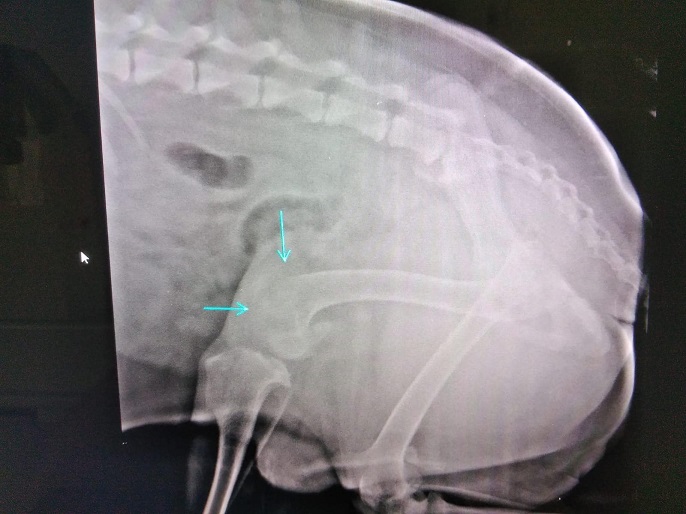

TORIN wurde von Aniela an einer Brücke gefunden, festgebunden mit einem kurzen Stück Kordel. Der super freundliche Kerl war aber quasi nicht im Stande, sich zu bewegen. Beide Hinterläufe konnten nicht richtig benutzt werden, die Knie schienen völlig lädiert zu sein. Schnell war klar, ein Hund wie TORIN (groß, riesen Handicap) wird wenig Chancen haben und kann vor Ort in Rumänien aber auch nicht ausreichend versorgt werden. Der Eulenhof am Niederrhein e.V. hat auch ihn als Gnadenplatzhund aufgenommen und dank seiner tollen Paten geht es nun stetig aufwärts. Neben einer guten Schmerztherapie bekommt TORIN regelmäßige Physiotherapie und kann sich auf dem großen Gelände des Eulehhofs frei bewegen und seine Muskulatur wieder gut aufbauen. Zusätzlich bekommt er sehr viele Zusatzpräparate. All das zusammen hat TORINS Bewegungsablauf massiv verbessert und er kann nun sogar mit anderen Hunden spielen. Er hat wirklich deutlich an Lebensqualität gewonnen und wir freuen uns so sehr, dass ein Notfall wie er diese Chance erhalten hat.